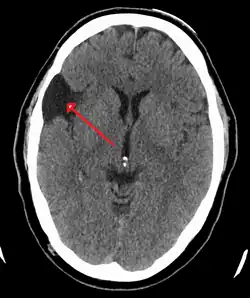

| An MRI of a 25-year-old woman with left frontotemporal arachnoid cyst. | |

Diagnosis is principally by MRI. Frequently, arachnoid cysts are incidental findings on MRI scans performed for other clinical reasons. In practice, diagnosis of symptomatic arachnoid cysts requires symptoms to be present, and many with the disorder never develop symptoms.